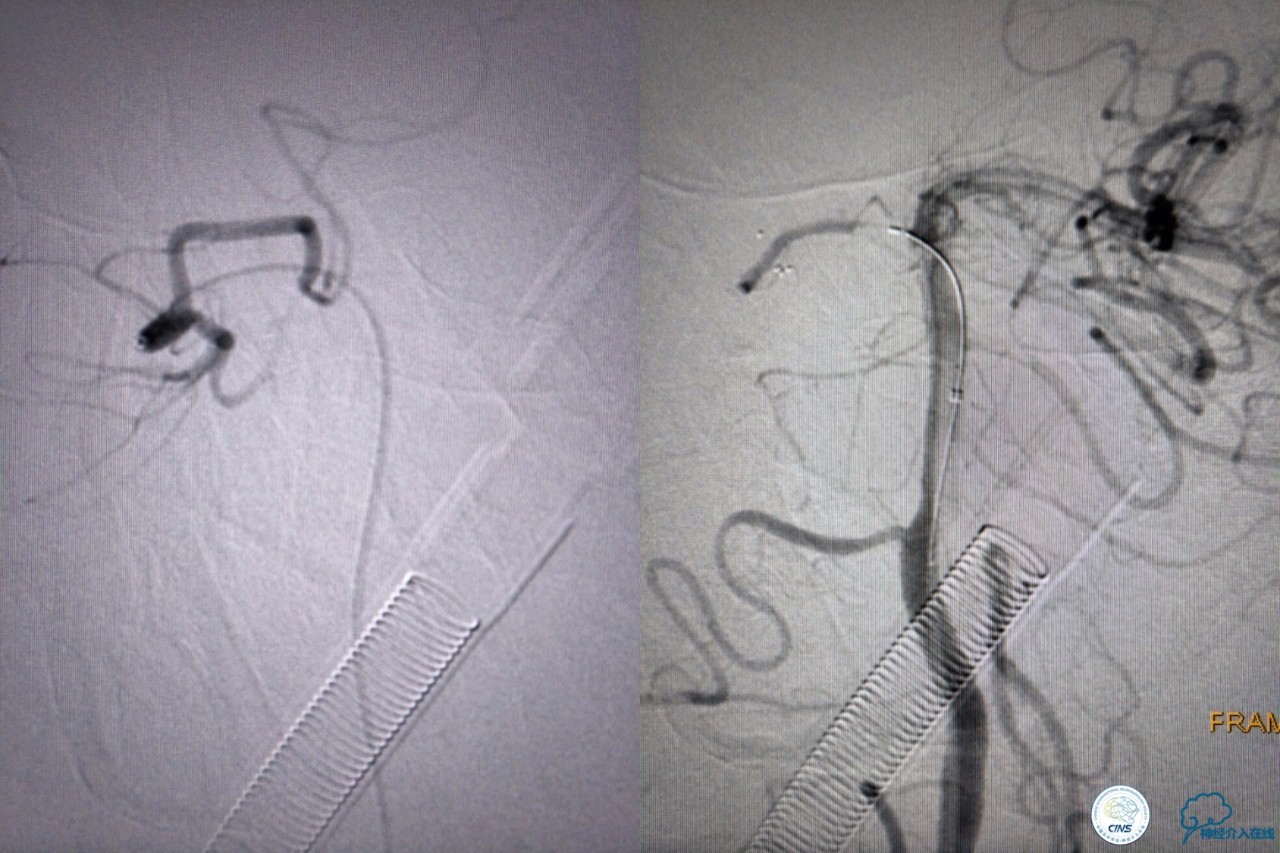

第三次取栓,支架放入左侧大脑后取栓。

第三次取栓后,左侧大脑后动脉开通,但是栓子再次栓塞右侧大脑后动脉,血栓在基地动脉顶端来回左右摆动,下一次,怎办?血栓负荷太多,可以使用solumbar技术,可以没有颅内导管,没办法,换用更大的支架6-20mm,但费用增加不少,与家属沟通后同意使用,第四次取栓:

血栓负荷还是很大,左侧大脑后再通,但右侧大脑后又闭塞,只能第五次取栓,支架放到右侧大脑后动脉更远。